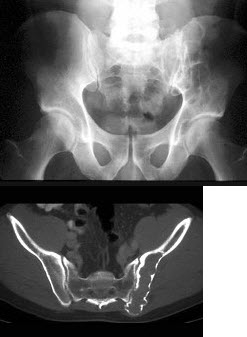

37、单项选择题

男,28岁,左髋疼痛不适三年余,结合图像,最可能的诊断是()

A.左髂骨动脉瘤样骨囊肿

B.左髂骨单纯性骨囊肿

C.左髂骨骨巨细胞瘤

D.左髂骨棕色瘤

E.左髂骨骨纤维性结构不良